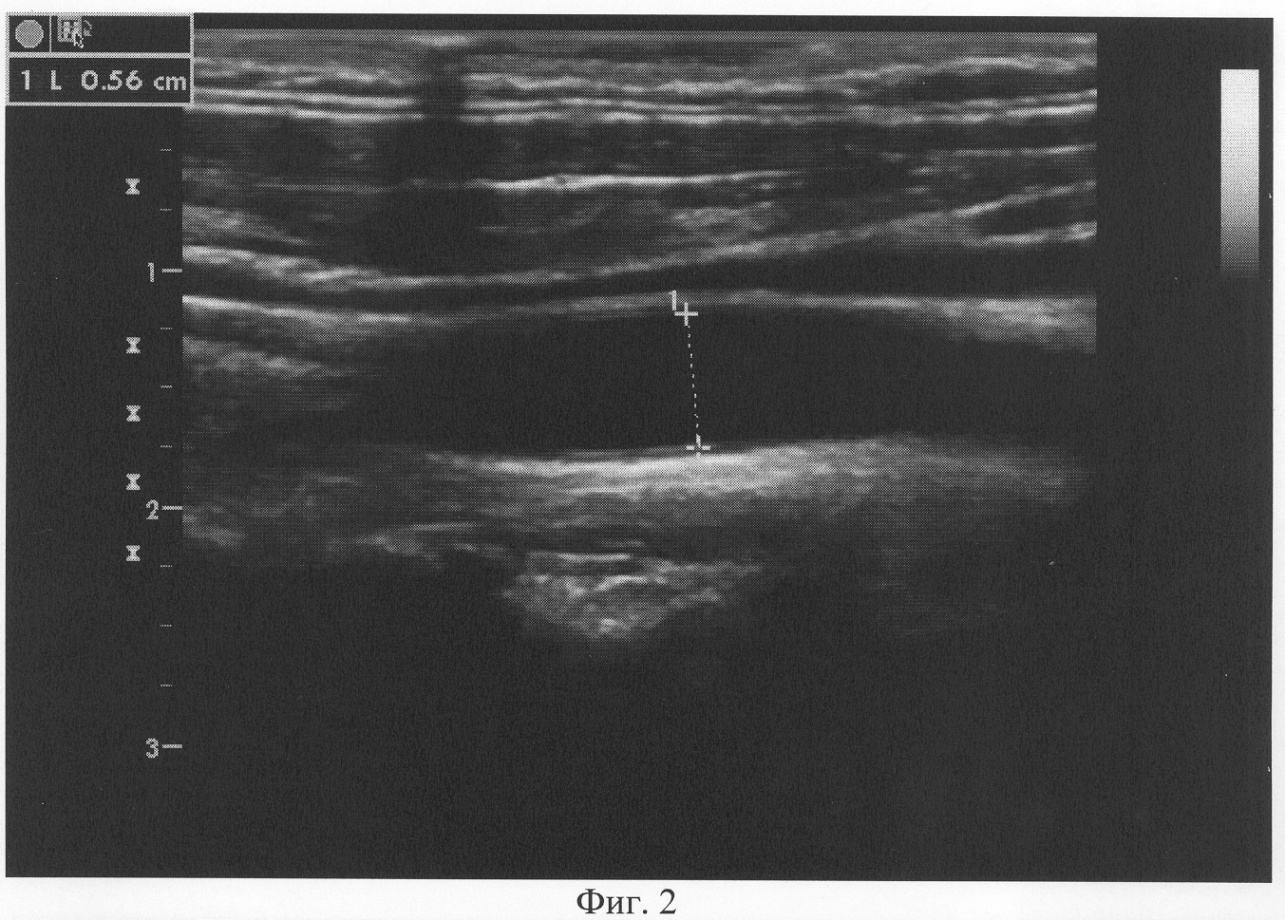

Больной П., 50 лет. Страдает бронхиальной астмой более 10 лет. Поступил в аллергологическое отделение краевой клинической больницы с жалобами на приступы удушья до 6-8 раз в сутки, ночью до 4 раз, купирует беротеком. Одышка при обычной физической нагрузке. Кашель с небольшим количеством вязкой мокроты, слизистого характера. Давящие, загрудинные боли днем до двух раз в сутки в течение 15 минут. При проведении диагностики предлагаемым способом d равен 1,76% (d0=0,56 см, d1=0,57 см). Больному сделана коронарография. На коронарографии сбалансированный тип, гемодинамически значимый стеноз диагональной ветви до 75%. Больному имплантирован коронарный стент («Vision» 3,0×18 мм). После лечения клинические симптомы ИБС не проявлялись. Диагноз при выписке: Бронхиальная астма, эндогенного генеза, тяжелое течение, стероидозависимая, обострение. Сопутствующий диагноз: ИБС, стабильная стенокардия 3 ф. кл. Гиперхолестеринемия 2В типа. Эндопротезирование ДВ («Vision» 3,0×18 мм) 18.06.04. СН I ст. (II ф.к. по NYHA). Гипертоническая болезнь 3 ст., риск 4.

Предлагаемый способ поясняется чертежами, где: на фиг.1 показан ультразвуковой датчик с изображением ОСА; на фиг.2 показан диаметр ОСА у больного ИБС (пример 1) до проведения ингаляции сальбутамолом; на фиг.3 – изменение диаметра ОСА после ингаляции сальбутамолом; на фиг.4 показан диаметр ОСА у пациента (пример 2) до проведения ингаляции сальбутамолом; на фиг.5 – изменение диаметра ОСА после ингаляции сальбутамолом; на фиг.6 приведена коронарограмма больного ИБС (пример 1); на фиг.7 – коронарограмма пациента (пример 2).